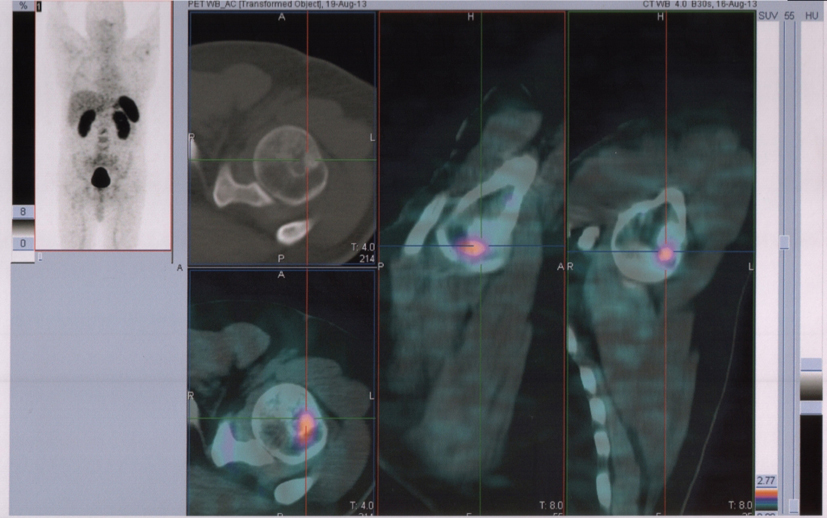

In August 2013, the patient referred to our hospital to investigate “in vivo” SSTR receptorial status. PET/CT evidenced several areas of increased uptake scattered through the whole skeleton, corresponding on CT with mostly mixed osteoblastic/osteolytic metastases (Fig. 3, 4).

![]() Click for large image | Figure 3. 68Ga-DOTANOC transaxial PET/CT at the level of left humeral head showing increased uptake of the radiopharmaceutical in a mixed metastasis (pointers). |